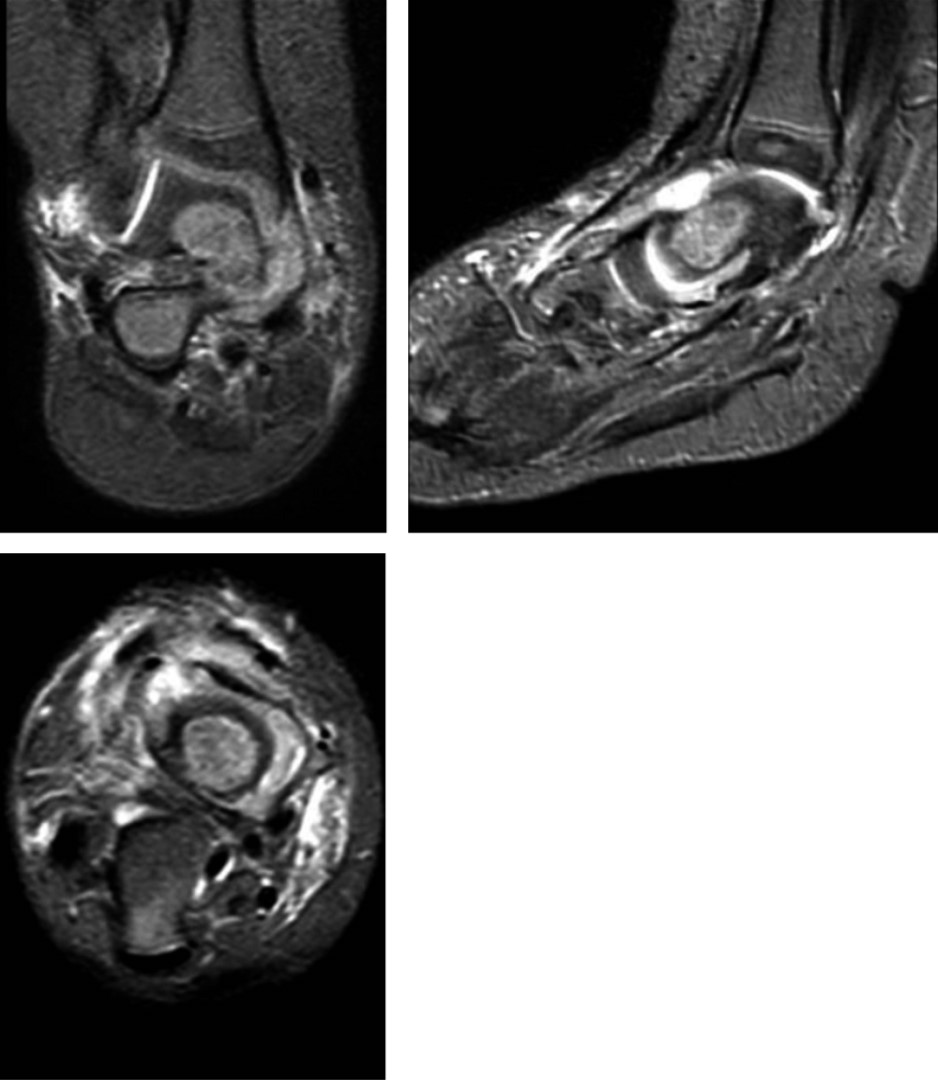

Figura 4